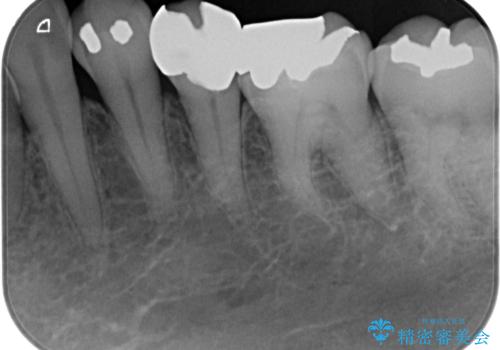

- 左下の奥歯に虫歯がある気がするとのことで来院された患者様です。

銀歯の裏側に虫歯が確認されました。

小さな段差も虫歯のリスクにつながります。

精度の良い補綴物を入れることで今後の虫歯リスクを抑えることができます。